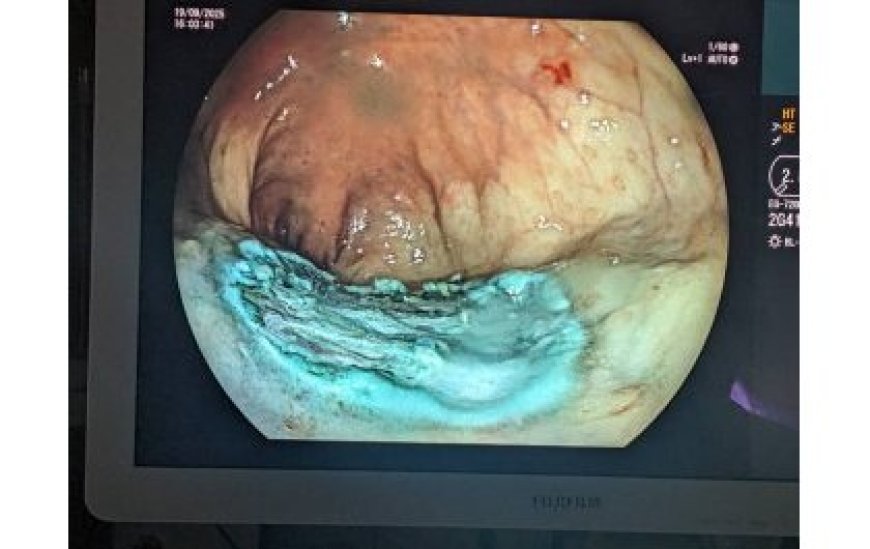

Uburyo ESD ikorwamo hafatwa ‘tube’ iriho camera n’utundi dukoresho bijyana bakayinjiza mu mubiri bayinjujije ahaca imyanda yo mu musarane noneho bakayigeza aho babonye ya kanseri.

Iyo ‘tube’ iba ihuje na mudasobwa zabugenewe kandi irimo n’inzira inyuramo amashusho y’ako kanya ya camera iri gufata ku buryo abaganga babona neza aho kanseri iri kandi bakabasha kuyikuramo badakomerekeje ibindi bice.